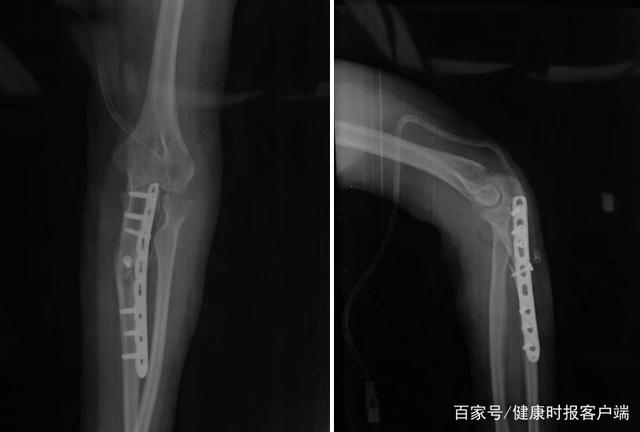

患者手术后肘关节正侧位X线片显示尺骨畸形矫正,内固定位置良好。受访者供图

“因为肘内翻畸形常见于儿童髁上骨折患者,畸形多来源于肱骨侧,通常采用肱骨髁上截骨内固定术治疗。然而该患者畸形来源于关节的内翻和尺骨的畸形,肱骨远端外翻角度正常,采用传统的肱骨髁上截骨无法解决患者的问题,为此我们决定结合治疗陈旧性孟氏损伤的治疗经验大胆地提出采用尺骨截骨内固定术治疗患者特殊类型的肘内翻畸形。”蒋协远教授说。

“整个手术大约经历了两个小时,目前患者整体恢复良好,经过手术之后,患者的肘关节屈伸和旋转都呈现出正常的水平。”蒋协远教授表示,目前我们国内骨科的治疗与国外相比还是不规范,但肘关节的诊断治疗以及并发症的预防,国内医务人员的水平跟国际相比,应该处于比较领先地位。之后,要推进复杂肘关节治疗的发展,医生们依旧需要将基础知识学好,积极的进行临床实践,这样才能真正为复杂肘关节疾病患者解决更多的难题。